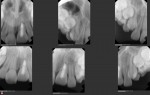

This is a 9yo girl with a high esthetic desire (wants to be a model/actor). She avulsed tooth #9 about 3 years ago, and she has been under treatment with other endodontists. I guess they attempted revascularization with MTA about year ago. #9 is ankylotic with a few mm’s infraposition. It is gray due to the MTA. #8 is slightly yellow/white due to calcification/obliteration but she says she feels cold testing and it is otherwise asymptomatic.

Gary for this patient a periodical film would help – the issue is NOT endo but the defect caused by eruption of the adjacent teeth – the PA film shows there is a vertical defect now that can be managed. The best thing would be to make sure there is a seal in the canal, then bleach the coronal part of the restoration, after which an additive type restoration to build out the rest of the clinical crown for esthetics – lithium disilicate would be my first choice of material to use.